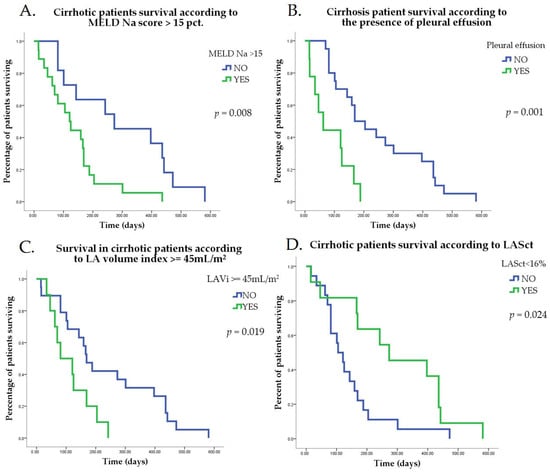

Journal of Clinical Medicine

Type A Aortic Dissection: From Diagnosis to Cardiac Rehabilitation